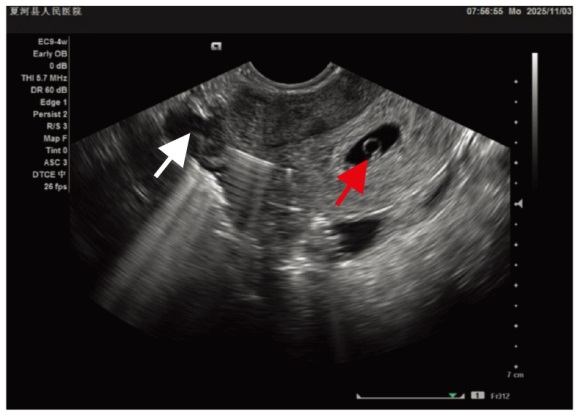

带器妊娠合并宫内节育器子宫穿孔一例

报告1例28岁女性,患者孕3产2,2018年和2022年分别足月自然分娩。放置节育器1年,因停经50 d,检查发现宫内节育器(intrauterine device,IUD)移位嵌顿7 d就诊,术前结合血人绒毛膜促性腺激素(human chorionic gonadotropin,hCG)和经阴道超声检查确诊为带器妊娠合并IUD子宫穿孔,在宫腹腔镜联合下完整取出IUD并行双侧输卵管结扎术及宫腔镜下负压吸引人工流产术,术程顺利,术后2 d出院。术后随访2周,hCG下降至正常范围。提示带器妊娠合并IUD子宫穿孔需综合考虑首次置入IUD、IUD置入位置不当、近期妊娠、金属IUD等因素进行准确诊断,采取合适的处理措施对患者预后至关重要。

We reported a case of the pregnancy with intrauterine devices (IUD) and uterine perforation. A 28-year-old female had a history of two full-term natural deliveries in 2018 and 2022, respectively and an IUD for one year. Due to 50 days of amenorrhea and 7 days of the displaced and incarcerated IUD, she came to our hospital for treatment. Preoperative examination, combined with serum human chorionic gonadotropin (hCG) and transvaginal ultrasound, confirmed the diagnosis of the pregnancy with IUD and uterine perforation. The IUD was completely removed, and bilateral tubal ligation was performed, under the combined hysteroscopy and laparoscopy while the negative pressure aspiration induced abortion was smoothly performed under hysteroscopy. The patient was discharged 2 days after the operation. After two weeks of postoperative follow-up, hCG was decreased to the normal range. It is suggested that the diagnosis of the pregnancy with IUD complicated by uterine perforation need a comprehensive consideration of multiple factors such as the first implantation of the IUD, improper placement of the IUD, recent pregnancy and metal IUD. Taking appropriate treatment is crucial for the prognosis of the patient.